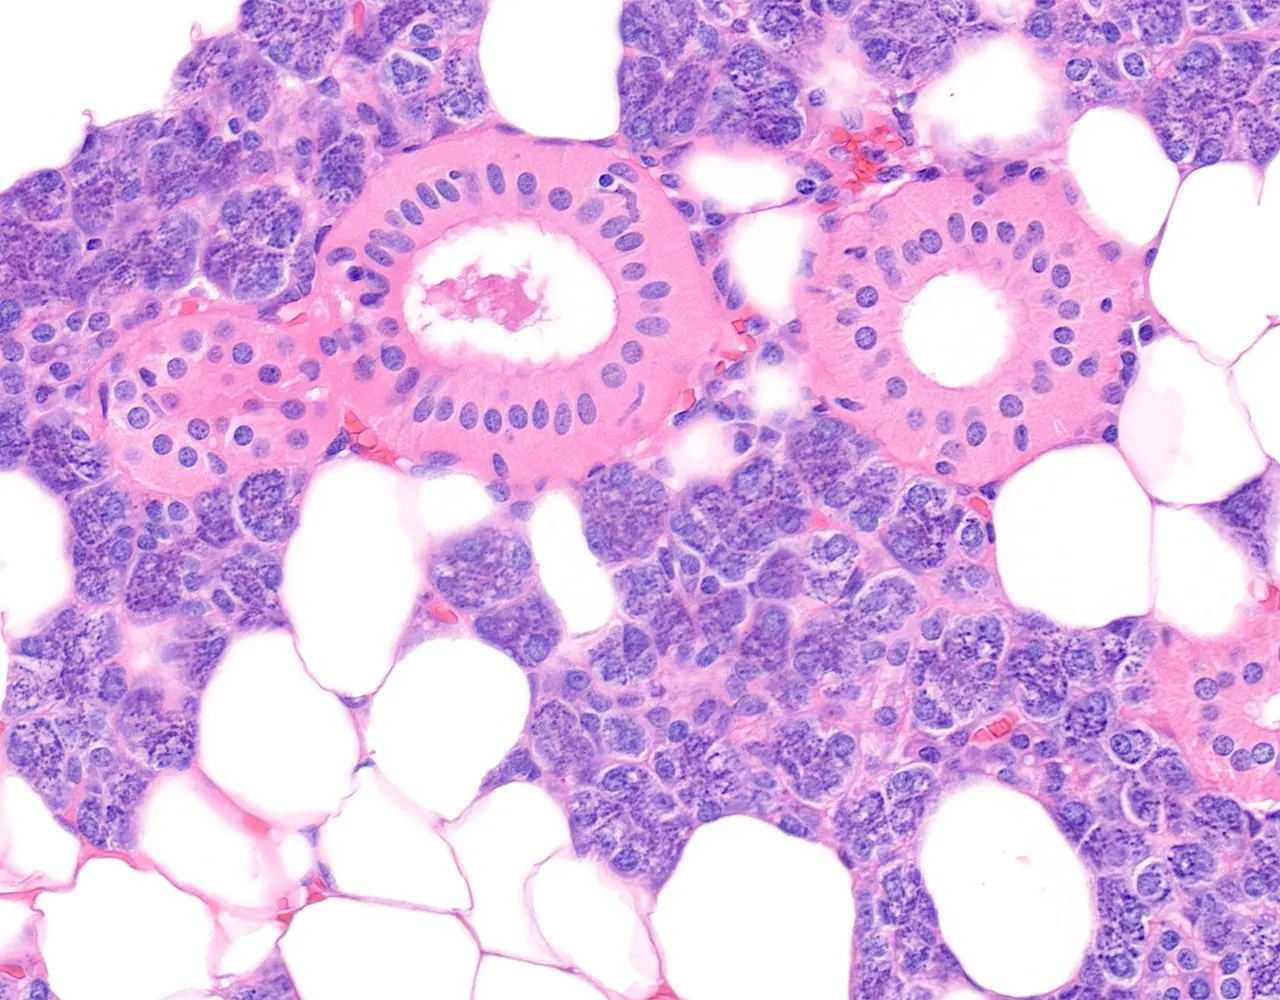

- Microscopically, the functional structure of a salivary gland consists of secretory acini and a duct system.